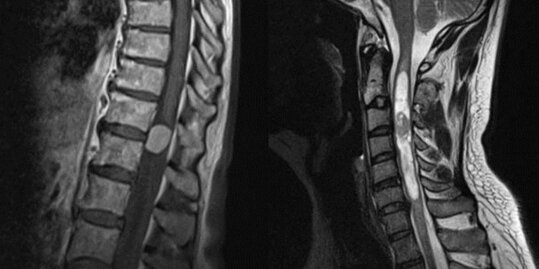

Tumoren des Rückenmarks und des Spinalkanals

Auch innerhalb des Spinalkanals können verschiedene Tumore auftreten. Diese können entweder außerhalb des Rückenmarks, wie z. B. Meningeome oder Neurinome, oder innerhalb des Rückenmarks lokalisiert sein, wie z. Beispiel Ependymome oder Astrozytome. Je nach Lokalisation und Größe können sie verschiedene Symptome verursachen. In einigen Fällen werden sie jedoch auch zufällig entdeckt. Die Therapie besteht in der Regel in einer operativen Entfernung, um das Neuauftreten oder Fortschreiten von neurologischen Ausfällen zu verhindern und Gewebe zur histologischen Untersuchung zu gewinnen. Je nach Tumorart kann sich postoperativ eine Nachbehandlung durch Bestrahlung und/oder Chemotherapie anschließen.